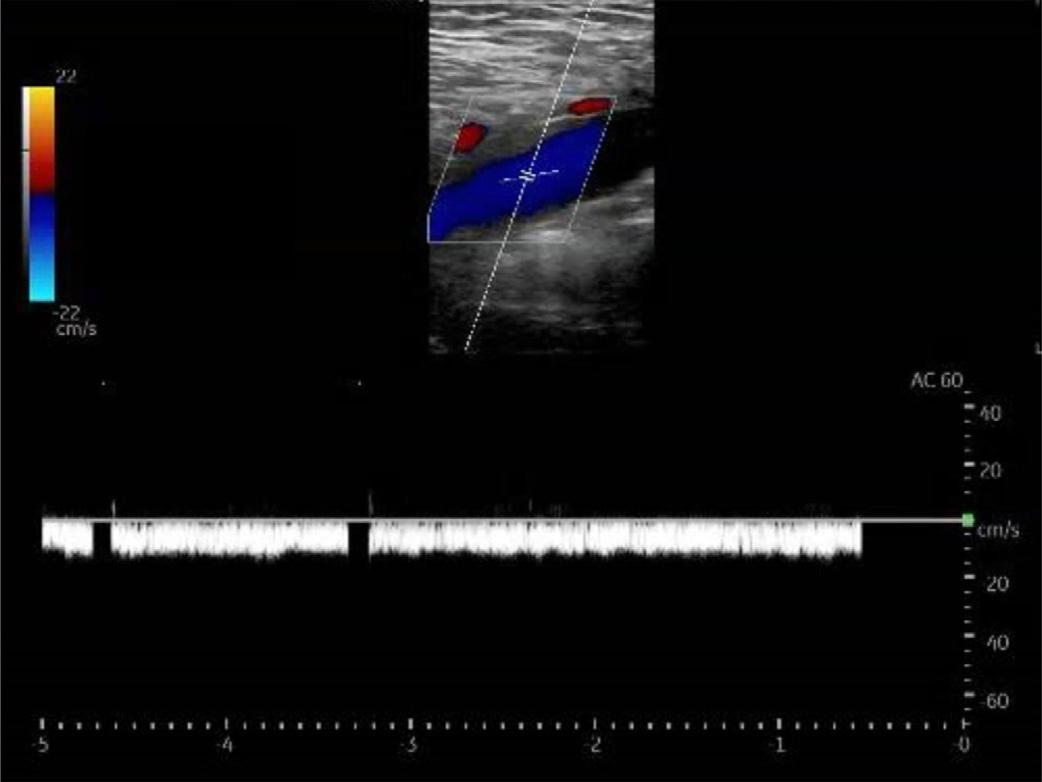

Hamzah M. Yusuf, Timothy Batchelor, Nicholas Ashenburg

298 Point-of-care Ultrasound Diagnosed Intraocular Breast Metastasis